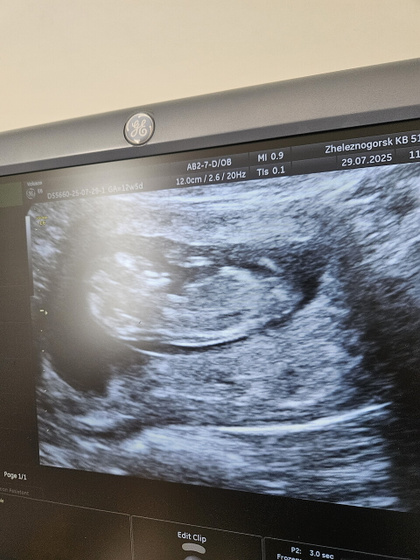

Сегодня прошла первый скрининг, по УЗИ все в норме. Такой маленький человечек уже там, послушала сердечко, такие классные эмоции. Срок по УЗИ конечно отстаёт на недельку от срока по месячным, но я так и думала, овуляция была поздняя? Сдала кровь, осталось дождаться только этих результатов и уже спать спокойно. Сказали до 15 числа должны прийти. Волновалась я конечно очень сильно, да и до сих пор еще волнуюсь) С дочкой так вышло, что пропустила первый скрининг и сразу пошла на второй, поэтому это все для меня впервые)

Ну самое главное, что у нас все хорошо)

Спасибо большое, да мы с врачом сразу это обсудили, я при первой явке ей сказала что срок скорее всего будет расходиться) она сказала, что неделя это не существенная разница)